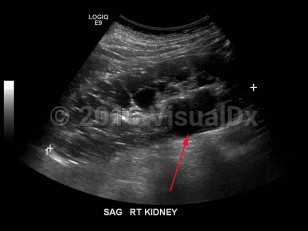

Imaging Studies image of Polycystic kidney disease - imageId=7911488. Click to open in gallery.  caption: '<span>Grayscale ultrasound image demonstrates enlarged right kidney with multiple cysts, some simple and others complex. The left kidney had a similar appearance.</span>'

Grayscale ultrasound image demonstrates enlarged right kidney with multiple cysts, some simple and others complex. The left kidney had a similar appearance.